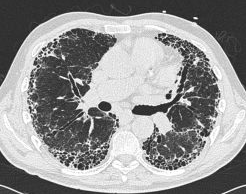

▲肺纤维化的胸部CT表现以胸膜下多发蜂窝、网格影及牵拉性支气管扩张为主要特征